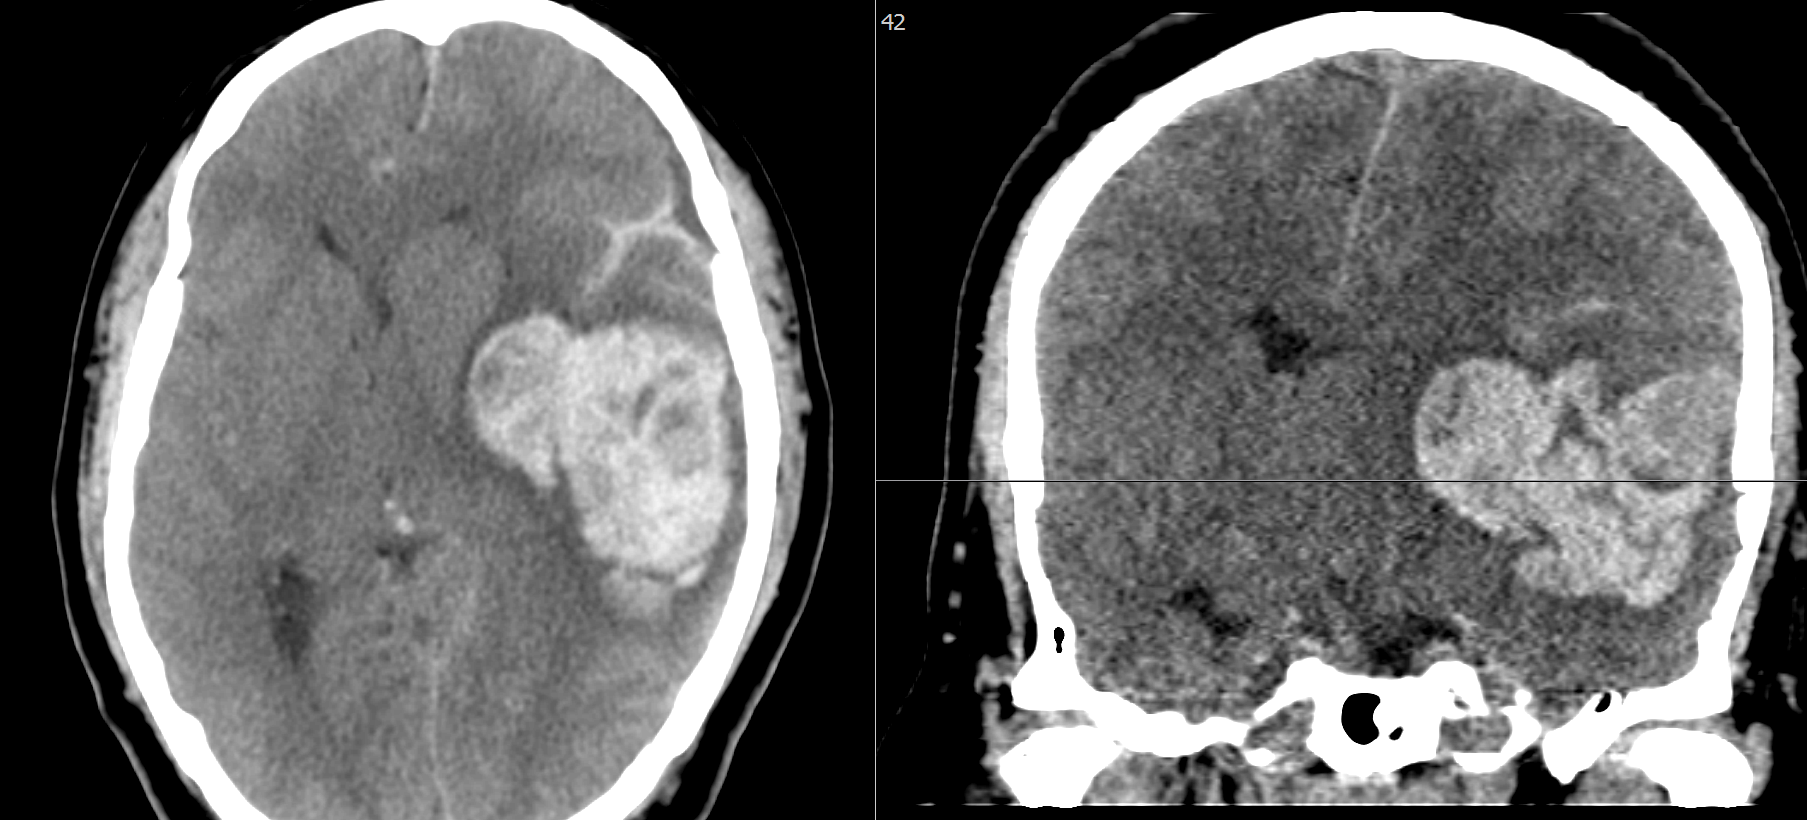

- En la última fase se procede a inyectar Gluebran que es detenido por los coils y forma un trombo distal a la marca de rotura del apollo.

Posteriormente a través del Prowler 10 se procede a crear la oclusión proximal para permitir la olla Express, para lo que empleamos:

- Una cesta inicial con un coil GalaxyG3 12

- Posteriormente se rellena con 3 coils Target Helical Nano (Figura 5)

En series finales de control se observa cierre completo de la fístula (Figura 7)